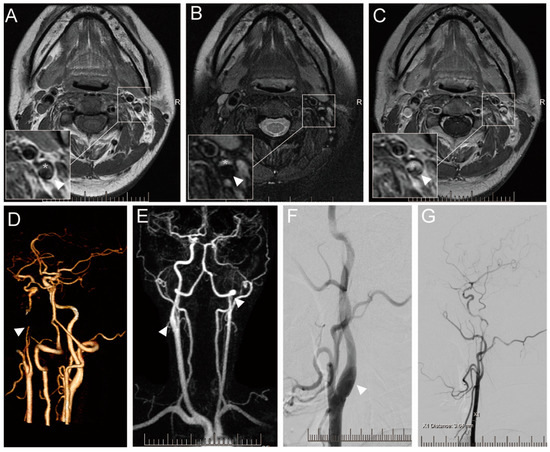

4. Imaging Characteristics of SCCAD